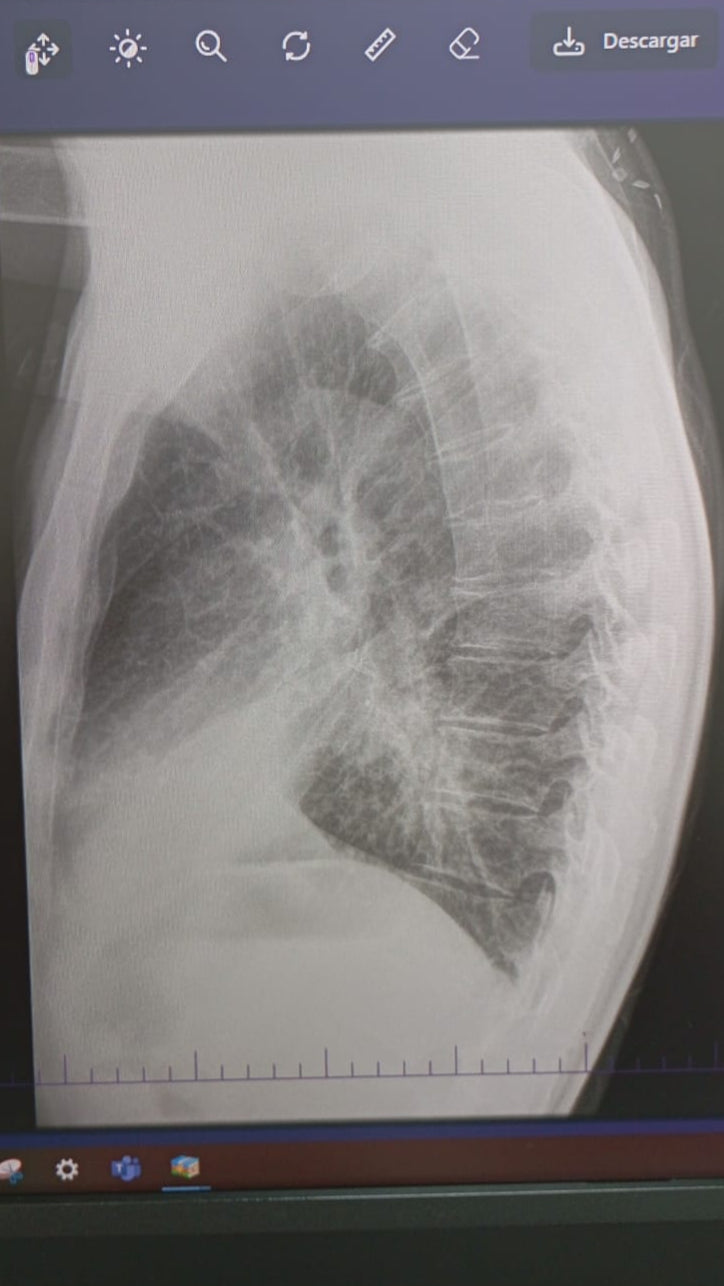

Lung Scan (Side View) - Showing the lung tumor activity

Lung Scan (Front View) - Showing the lung tumor activity

In December of 2024, what started as a small cough became our worst nightmare. With limited access to health care, we paid what exams we could out of pocket.Scans confirmed a tumor, this time on his bronchus, where air flows. This tumor was slowly suffocating my dad.He would have coughing episodes so bad he could barely breathe.

My dad had to leave the country in May and 3 months later he has yet to start any treatment.Due to Colombia's healthcare system, that means months of waiting for each test with insurance.While he waited, the cancer spread to his kidney. Now to his brain. Two tumors are causing him to loose feeling from the left side of his face, his mouth, and his eye. He is at risk for paralysis.

He has been hospitalized multiple times, coughing blood, in excruciating pain, all while being thousands of miles away from us. Right now my dad urgently needs radiation, chemotherapy, medications, and housing close to the hospital so he can get treatment safely.